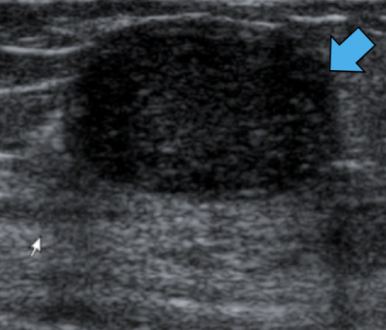

Solid mass

(as on USS; solid tissue appears as varying shaded of grey)

Malignant mass